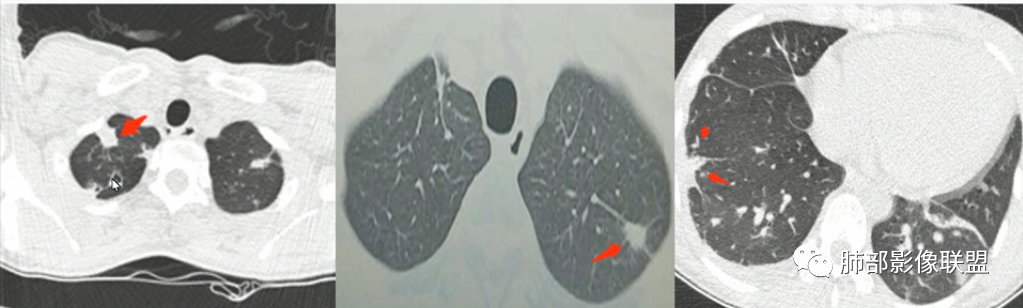

少年患者,游泳后发热畏寒,呼吸困难,两肺弥漫分布结节及磨玻璃影,考虑寄生虫感染,钩体病?

外伤后与河水接触史,病灶分布随机,点晕征,淋巴低,CRP、降钙素高。休克血压。考虑感染性病变:钩端螺旋体病

青少年,双肺多发结节斑片影,肝密度减低,有下水的经历,PCT太高,考虑感染性疾病,钩体病?金葡菌脓毒性栓子?

青少年,河水不知道是否污染,气道分布斑片影,pct,crp高,g-杆菌,周围似见晕征,脓毒性肺栓塞,金葡,钩体感染

青少年,高处跳落游泳史,左侧盆部疼痛(怀疑皮肤损伤),畏寒发热,CRP和Pct显著升高,感染性休克表现(提示革兰阴性杆菌),双肺叶外周分布为主棉絮状结节及斑片影,GGO密度,边缘清,间质及实质改变,病灶内细网格影,见供血血管证,分布特点双肺叶Spe表现,考虑大肠杆菌导致血行感染,血培养检查!

男14岁,2天前下河游泳史,发热;两肺近外带可见磨玻璃密度影,边缘疑似晕征,结合实验室检查,符合感染,倾向真菌感染,支持肺钩端螺旋体病。

青少年,2天前下河游泳后畏寒发热,两肺外周胸膜下分布多发大小不等结节、斑片及磨玻璃,边缘模糊,考虑血流性感染,钩体?金葡?

青少年男性,2天游泳后发热,双肺多发斑片状,结节状阴影,多分布肺外带,血道来源,部分病灶边缘可见磨玻璃影,患者有明显脂肪肝病史,考虑.感染性病变,金黄色葡萄球菌?钩体?肺克?

青少年,河沟游泳后急性发病,左侧髋部疼痛,双肺弥漫地方结节、斑片模糊影,CRP、PCT明显增高,考虑钩体病,鉴别血播金葡

PCt>200,脓毒血症了,有无皮肤损伤?诱因游泳,高处跳水,与水有关,影像为多发毛玻璃结节,有细网格样改变,内可见支气管影,所以是间质改变➕肺泡渗出;结节分布是随机分布,血源性。与临床相对应。感染性病变,pct不支持病毒排除。细菌,金葡?军团?需复查看看病情转变。有无三红三痛,如有,钩也可能。寄生虫待排。

急性起病,游泳史,寒战发热,感染指标明显升高,胸部CT双肺多发磨玻璃影,实变,内可见支气管扩张,大致呈间质改变,随机分布,首先考虑感染性疾病。

青少年,多发斑片影,有游泳史,伴CRP及PCT升高,首先考虑血源性葡萄球菌感染

年轻患者,急性起病,高处跌下,皮肤损伤,两肺胸膜下多发实变,边缘见磨玻璃影,部分实变呈楔形,实变内见粗网格影,部分实变见反晕征,综和病史考虑感染性病变,影像上符合脓毒性肺栓塞,支持血源性金葡菌感染,鉴一下COP

青年人,有游泳史,畏寒发热,双肺内及胸膜下多发实变,边缘见磨玻璃密度影,部分呈反晕征,内可见多发网格样改变,考虑感染性病变,金葡菌感染

双肺叶结节及斑片状磨玻璃样密度,边缘清,外周分布为主,部分见供血血管,分布特点符合Spe表现,青少年,高处跳落游泳史,左侧盆部疼痛,畏寒发热,CRP和Pct显著升高,考虑血行感染,金葡?至于大家考虑的钩端螺旋体病和嗜水单胞菌不是太了解

青少年发病急,高热,双肺多发斑片状磨玻璃影,边界模糊,以胸膜下为主,考虑感染性病变,金葡菌可能

青年,游泳,盆骨处疼痛”原因?”,畏寒,发热,Pct明显升高。双肺多发斑片,结节影。胸膜下也有。考虑血播。金葡可能大

游泳,高处跳下盆骨疼痛,肺上血播及气道均有,符合感染性病变,吸入性病变,金葡菌肺炎要考虑

流心明智:

男,14岁,高处跳下,游泳后畏寒。胸部CT:两肺多发斑片影、结节影;沿支气管血管束分布,胸膜下也有;密度以GGO为主,部分为mGGO;边缘部分清楚,大部分模糊;内可见网格影、支气管充气征。考虑:SPE?肺水肿?鉴别淋巴瘤。